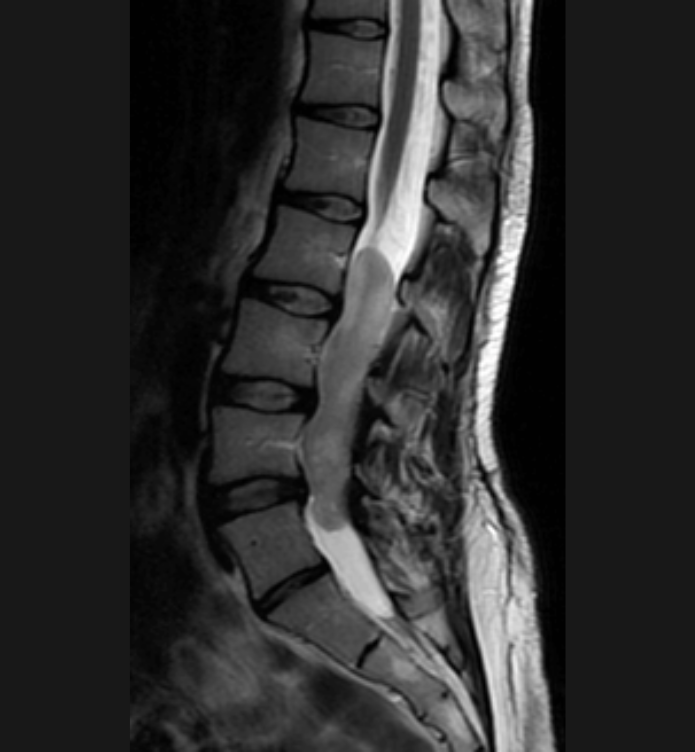

Basit Omurga ve Omurilik Anatomisi Omurga, 33 adet omur kemiğinden oluşur. Bu kemiklerin 7 tanesi boyun omuru, 12 tanesi sırt omuru, 5 tanesi bel omurudur. Beş tanesi birleşmiş olarak sakrum denilen kemiği ve 4 tanesi yine birleşmiş olarak koksiks denilen kuyruk sokumu kemiğini oluşturur. Omurganın görevi omuriliği korumak ve gövdeyi dik pozisyonda tutmak için destek […]